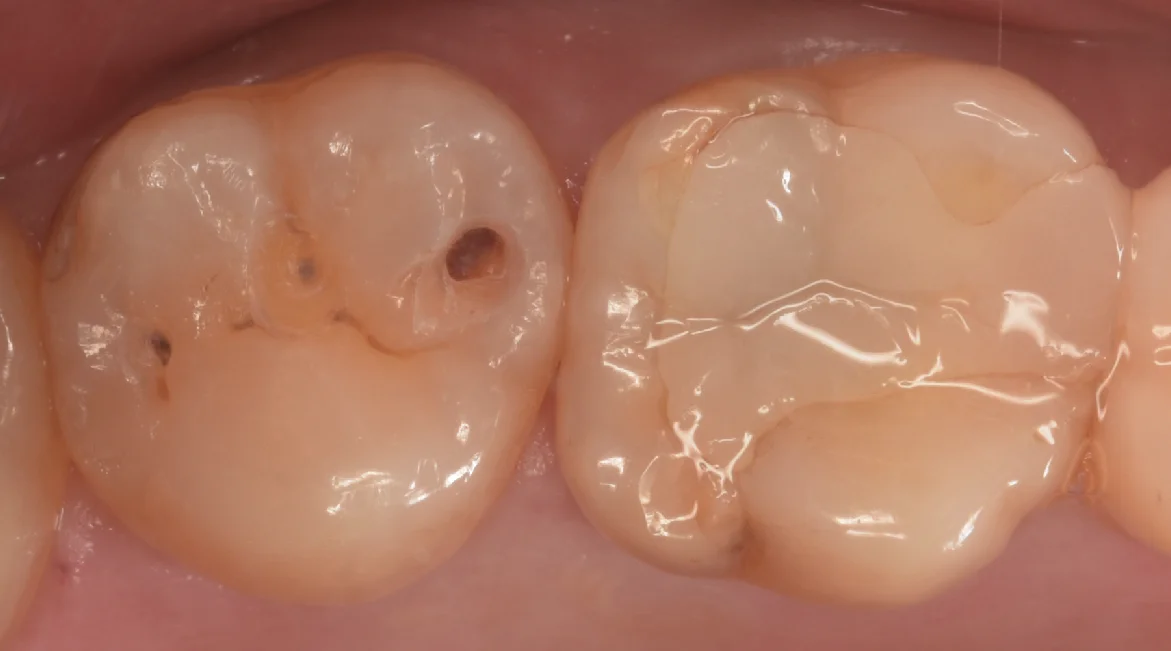

まずは術前からです。

写真左側の歯を治療しました。

中心に小さく保険のCRを行なっており、手前の歯の間側・後ろの歯の間の小さな穴にそれぞれ虫歯があります。